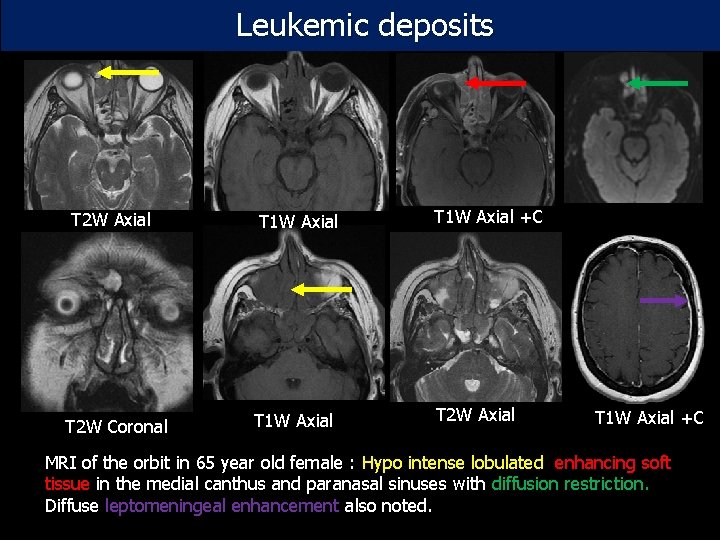

Leukemic deposits T 2 W Axial T 1 W Axial +C T 2 W Coronal T 1 W Axial T 2 W Axial T 1 W Axial +C MRI of the orbit in 65 year old female : Hypo intense lobulated enhancing soft tissue in the medial canthus and paranasal sinuses with diffusion restriction. Diffuse leptomeningeal enhancement also noted.